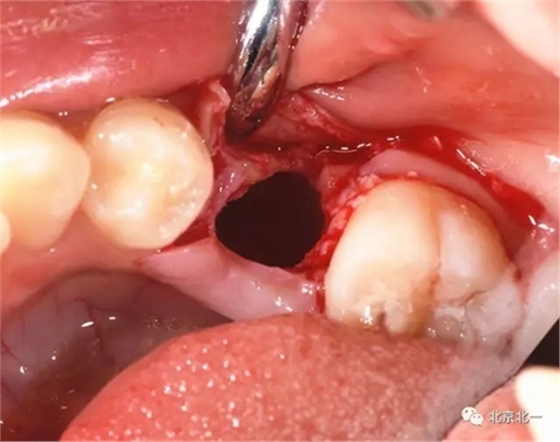

埋伏牙專(zhuān)用攪碎機(jī)攪碎牙齒